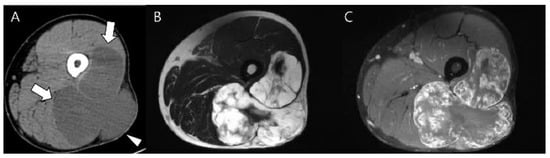

3.1. Distinction between Enchondroma and ACT

3.2. Biopsy or Follow-Up? Questions for Incidental Cartilage Lesions in the Long Bones